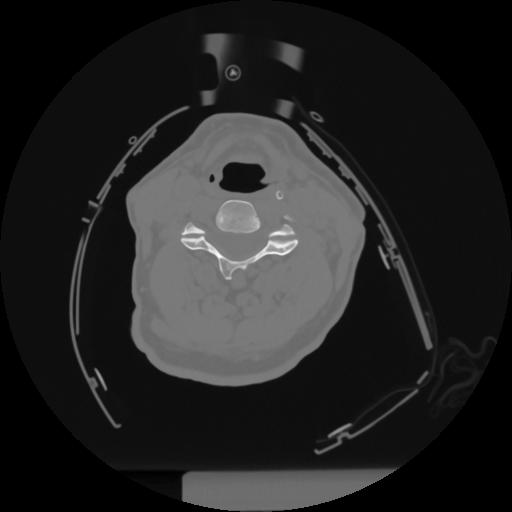

12 P.BLANDAS,,Vol,0.5,P.BLANDAS,,